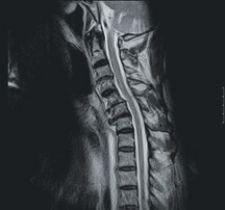

Siemens Medical Solutions has introduced syngo BLADE, the newest TIM (Total Imaging Matrix) technology-powered MRI software. The technology is capable of imaging in neurological and orthopedic procedures. In cases of severe movement, syngo BLADE motion correction application allows facilities to increase patient throughput and decrease costs.

According to the company, the technology is ideal for pediatric and difficult-to-manage patients in neurological and orthopedic imaging because it is not affected by flow and motion. This application measures and corrects any motion, providing clear images by the continuous acquisition of low-resolution images. With the low sensitivity to movement, it allows medical professionals to focus on reducing sedation rates for pediatric and anxious patients, which in some cases can increase time efficiency.